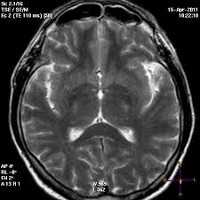

- Инструментальные методы. Используются нейрофизиологические и нейровизуальные методики: ЭЭГ, РЭГ, УЗДГ сосудов шеи и головного мозга, рентгенография шейного отдела позвоночника, МРТ головного мозга, МРТ сосудов головного мозга. Результаты подтверждают морфологические и функциональные изменения ЦНС.

- Томография. Проанализировать степень морфологических изменений можно при помощи МРТ головного мозга. Этот метод также позволяет дифференцировать энцефалопатию от других церебральных заболеваний: болезни Альцгеймера, внутримозговой опухоли, энцефалита, рассеянного энцефаломиелита, инсульта, кортикобазальной дегенерации, болезни Крейтцфельдта — Якоба и пр.